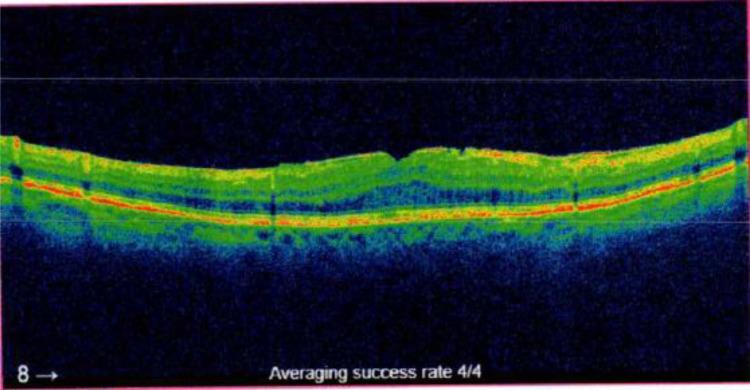

A retrospective chart review was conducted on patients aged 18 and above diagnosed with postoperative or uveitic CME via optical coherence tomography from January 1, 2016, to December 31, 2023. Among these eligible patients, we investigated those treated with non-steroidal anti-inflammatory drugs (NSAIDs) and/or corticosteroids. The primary outcome was the duration until complete resolution of CME. Secondary outcomes included improvement of CME and the likelihood of CME recurrence after treatment. Statistical analysis involved ANOVA and Tukey's HSD test to compare treatment efficacy.

对2016年1月1日至2023年12月31日期间通过光学相干断层扫描诊断为术后或葡萄膜炎性CME的18岁及以上患者进行回顾性病历审查。在这些符合条件的患者中,我们调查了接受非甾体类抗炎药(NSAIDs)和/或皮质类固醇治疗的患者。主要结局是CME完全消退的持续时间。次要结局包括CME的改善情况以及治疗后CME复发的可能性。统计分析采用方差分析和Tukey's HSD检验来比较治疗效果。